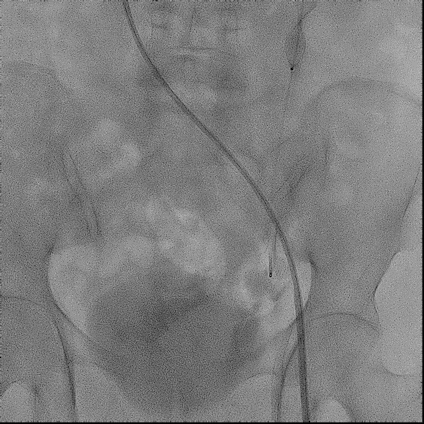

手术过程(一):

右股静脉穿刺,交换8 F-90 cm长鞘导入A3段,造影见A3段远端显影良好,中段动静脉瘘高速血流,可见“瘤槽”显影。